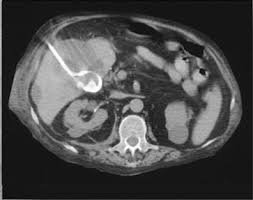

Η διαδερμική χολοκυστοστομία είναι σήμερα η πιο διαδεδομένη και «κλασική» μορφή χολοκυστοστομίας:

- Εκτελείται από επεμβατικό ακτινολόγο ή χειρουργό.

- Χρησιμοποιείται τοπική αναισθησία και ήπια μέθη, όχι γενική αναισθησία.

- Υπό υπερηχογραφική ή/και αξονική καθοδήγηση:

- Διαπερνάται το δέρμα και, συνήθως μέσω του ηπατικού παρεγχύματος, εισερχόμαστε στη χοληδόχο κύστη.

- Αναρροφάται χολή/πύον και αποστέλλεται για καλλιέργεια.

- Περνά οδηγός σύρμα και πάνω σε αυτό τοποθετείται λεπτός καθετήρας (pigtail) που καθηλώνεται στο δέρμα και συνδέεται με σακουλάκι συλλογής.